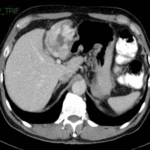

Metástasis

Las metástasis son el tumor hepático maligno más frecuente y ocurren hasta 18 veces más que los tumores primarios. Como consecuencia de la circulación portal el hígado es el órgano en el que más frecuentemente se localizan metástasis. Entre el 60% y el 80% de los pacientes con antecedentes de carcinoma colorrectal, carcinoma de páncreas, cáncer de mama y otros tumores como los neuroendocrinos desarrollan metástasis hepáticas. La supervivencia de los pacientes con metástasis hepáticas depende de su extirpación quirúrgica.

La evidencia de las lesiones hepáticas obedece tanto al número y localización dentro del hígado, como a la presencia o no de enfermedad extrahepática. Esto último es importante en el proceso de selección de aquellos pacientes a los que se les debe o no ordenar una cirugía hepática. En la tomografía sin contraste las metástasis suelen ser iso o hipodensas respecto del resto de parénquima, salvo en casos de sangrado o calcificación intralesional en que pueden ser hiperdensas. Podemos observar calcificaciones en metástasis de tumores mucinosos del tracto gastrointestinal o en metástasis de ovario, mama, pulmón, riñón y tiroides.(18) Las metástasis suelen tener el mismo comportamiento que el tumor de origen, suelen ser hipovasculares en tumores de colon, pulmón, adenocarcinoma de páncreas y en tumores de vejiga y próstata. Se observan lesiones hipervasculares en tumores primarios de tiroides, tumores neuroendócrinos (carcinoide, tumor de islotes pancreáticos, feocromocitoma) y en melanoma, cáncer renal, coriocarcinoma y sarcomas.(18-19)

Dentro de los patrones de reforzamiento de las metástasis lo más frecuente que podemos encontrar en fase arterial es la captación periférica y continua (por efecto de parasitación de la lesión y reacción desmoplástica/inflamatoria del parénquima adyacente), metástasis homogéneamente hipercaptantes (suelen ser menores de 1,5 cm), metástasis heterogéneas por fibrosis y necrosis central (> 3 cm) o con mínima captación periférica (lesiones hipovasculares).(18) En las fases portal y venosa tardía el patrón más frecuente es la captación progresiva incompleta. En menor grado se observan lesiones que se hacen isodensas con el resto de parénquima o persistencia de una mínima captación periférica (Anexo 17). El fenómeno de lavado (washout) periférico se ha descrito como hallazgo típico de metástasis, consiste en la desaparición del contraste en la periferia de la lesión en fases retardadas, es más frecuente en las metástasis hipervasculares, especialmente en tumores neuroendocrinos. Supone una mejor vascularización arterial y venosa en la periferia, donde se sitúa el tumor viable, respecto al centro de fibrosis o necrosis.(18-22)